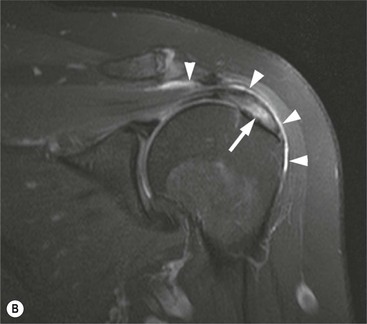

The primary sign of a rotator cuff FTT is a focal deficiency of the tendon (Figs. 46-4 and 46-5). This nearly always occurs at the tendon insertion on the tuberosity. The margins of the tear are best delineated when there is fluid within the tendon defect. Secondary signs of an FTT include the presence of fluid in both the GHJ and SAB, and flattening or concavity of the subacromial fat plane.

PTTs are less reliably demonstrated by both MRI and US, and it may be difficult to differentiate tendinopathy from partial tears. Focal clefts, tears, or tendon thinning affecting the articular margin of the footprint of the tuberosity are most common (Figs. 46-6 and 46-7). Tendon thickening is not always present. It is important not to mistake magic angle phenomenon on short TE MR sequences or anisotropy on US as evidence of tendinopathy.2